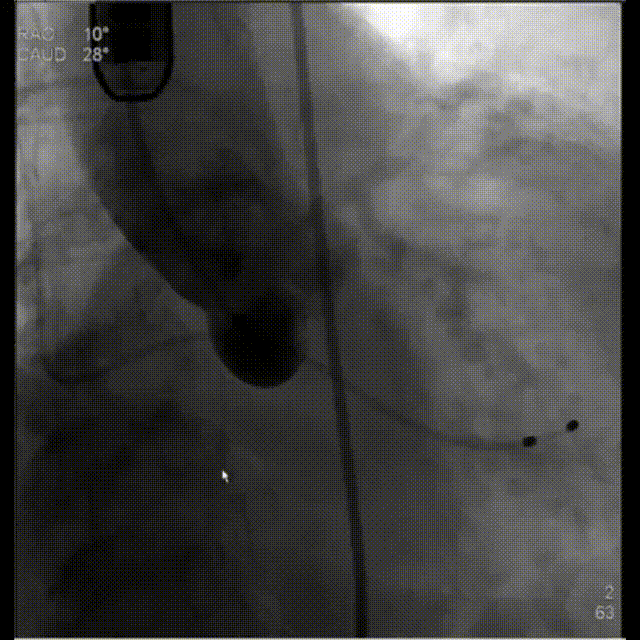

3.根据术前CT评估,球囊预扩角度为LAO 21° CRA 9°(左冠切线位)充分评估冠脉灌注情况,释放角度为RAO 10° CAU 28°(右足位)。使用18mm球囊预扩,根据沛嘉TaurusElite®产品设计特点采取瓣环平面下0-2mm高度释放策略。

主动脉根部造影

第一次释放